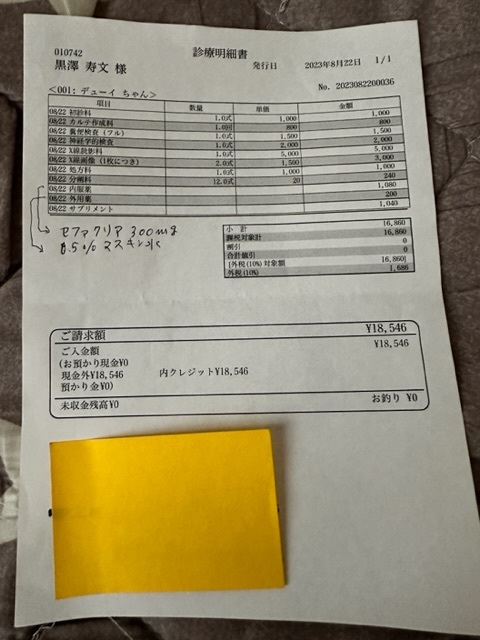

実際にかかった治療費

★

★

★

★

▶︎ 4. 掲載している資料について

ページ上に掲載している診断書や診療明細書などの資料は全て動物病院から掲載の許諾を得ております。